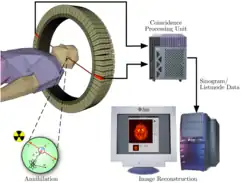

Trifft ein durch Zerfall des Radionuklids entstandenes Positron auf ein Elektron, werden beide vernichtet (Annihilation). Es entstehen zwei Photonen (Gammastrahlung), die sich in einem Winkel von praktisch genau 180° voneinander entfernen. Diese Vernichtungsstrahlung trifft gleichzeitig (koinzident) zwei Detektoren. Dadurch kann auf rechnerischem Wege durch Einsatz eines Computers der Ort der Positronenemission eingegrenzt werden. Werden in zwei Detektoren γ-Quanten der richtigen Energie zeitgleich nachgewiesen, wird dies als Positron-Elektron-Vernichtung an einem Punkt auf der Linie zwischen den beiden Detektoren interpretiert (sogenannte Line Of Response (LOR) bzw. Koinzidenzlinie). Die Technik der Positronen-Emissions-Tomographie zielt darauf ab, eine möglichst hohe Rate echter solcher Ereignisse zu detektieren und gleichzeitig die Rate von Fehldetektionen niedrig zu halten.

Ähnlich wie bei der Szintigrafie wird dem Patienten zu Beginn einer PET-Untersuchung ein Radiopharmakon verabreicht, meist durch Injektion in eine Armvene. Die PET verwendet Radionuklide, die Positronen emittieren (β+-Strahlung). Bei der Wechselwirkung eines Positrons mit einem Elektron im Körper werden zwei hochenergetische Photonen einer Energie von je 511 keV (entspricht der Frequenz 123 EHz und der Wellenlänge 2,43 pm) in entgegengesetzte Richtungen, also mit dem Winkel 180 Grad zueinander, ausgesandt (Vernichtungsstrahlung). Das PET-Gerät enthält viele ringförmig um den Patienten angeordnete Detektoren für die Photonen. Das Prinzip der PET-Untersuchung besteht darin, Koinzidenzen zwischen je zwei gegenüberliegenden Detektoren aufzuzeichnen. Typische Zeitfenster der Nachweiselektronik betragen hierfür 4,5 bis 15 Nanosekunden. Aus der zeitlichen und räumlichen Verteilung dieser registrierten Zerfallsereignisse wird auf die räumliche Verteilung des Radiopharmakons im Körperinneren geschlossen und eine Serie von Schnittbildern errechnet. Häufige Anwendung findet die PET bei stoffwechselbezogenen Fragestellungen in der Onkologie, Neurologie sowie Kardiologie.